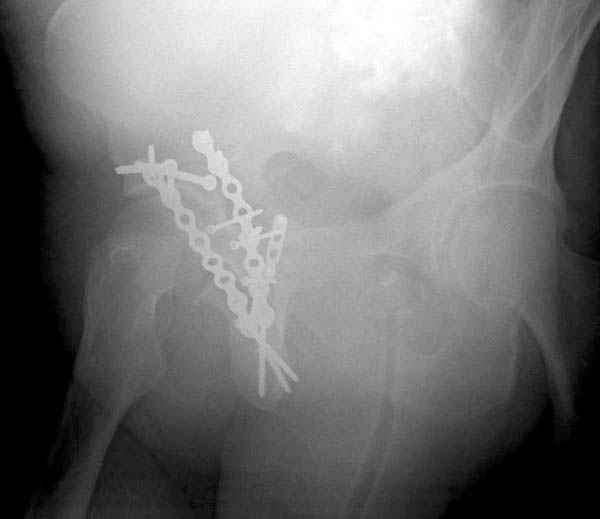

На 20-е сутки снял гипс, одел фиксирующюю

ортопедическую повязку. Вот контроль. Как видно, стояние хорошее, уже формируется костный мозоль.

Думаю еще недели 3 продолжать фиксацию.

-Головка плеча в небольшом варусе или это

проекционное?

Да, там имеем небольшой варус, надеемся, что в будущем проблемы не будет.

Там множество обычных 2.7 мм шурупов, потом идет фиксация основными пластинами.

Полную нагрузку разрешаем в 12 недели, хотя движения в суставе с первых дней.

Снимки здесь....